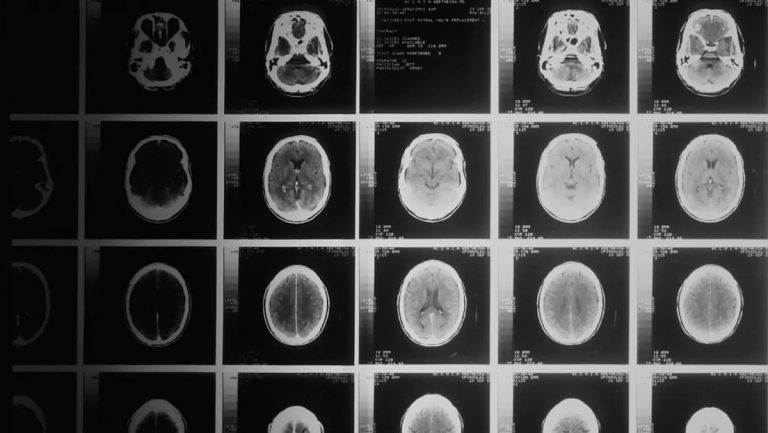

Un equipo de científicos de la Universidad Johns Hopkins, EE.UU., desarrolló recientemente un novedoso gel para administrar medicamentos,...